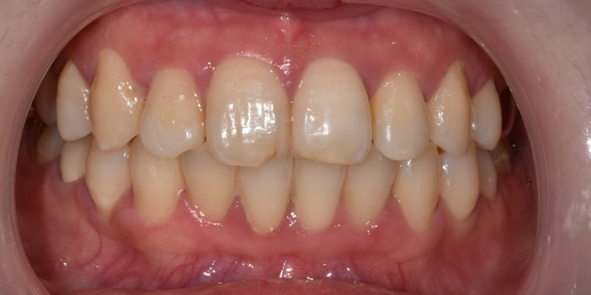

29세 여성

최소삭제 라미네이트

(전) 2022-08-02 (후) 2022-08-11

교정 후 치아 배열은 고르게 개선되었지만 치아 모양과 색상이 마음에 들지 않아 라미네이트 진행하신 환자분인데요.

고른 치아배열로 인해 최소삭제 라미네이트로 시술해드렸던 환자분입니다.